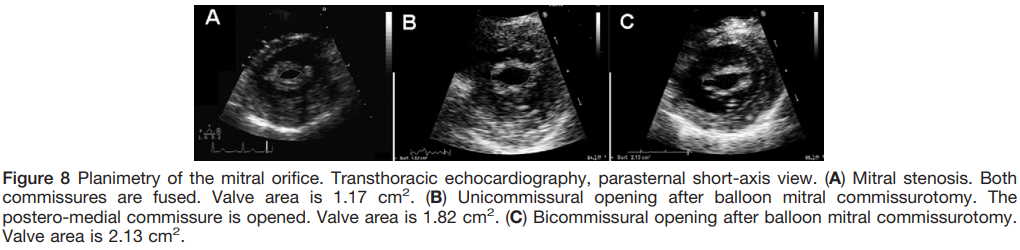

MVA Planimetry

- Direct measurement of the mitral valve orifice at the level of the mitral leaflet tips, including open commissures, from parasternal short-axis view

- It should be perpendicular to the plane of the orifice and have an elliptical shape

- Measured in mid-diastole

- Reference measurement of MVA

Valve anatomy -parasternal short-axis

- Commissural fusion can be assessed at the same level as planimetry